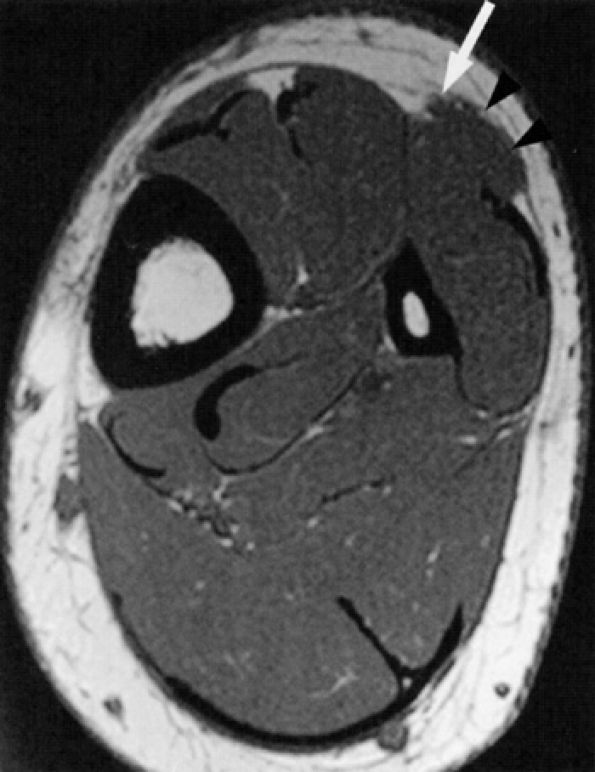

FIGURE 6.49 ● Tarsal tunnel syndrome and medial plantar nerve denervation edema due to proliferative synovitis. (A) Axial T2-weighted image demonstrates a synovial mass (asterisk) in the tarsal tunnel. (B) Sagittal T2-weighted fat-suppressed image illustrates denervation edema in the flexor digitorum brevis muscle (asterisk). Note associated osteoarthritic changes in the anterior tibiotalar joint (arrow).